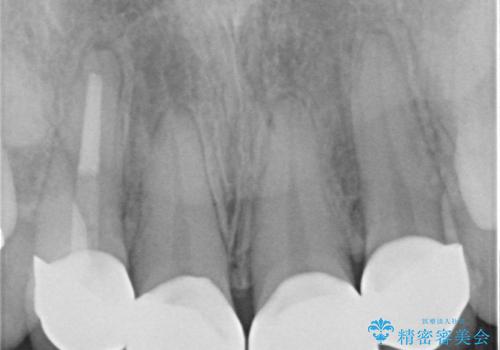

- 神経をとった前歯の変色や、前歯の充填物の変色が大きくなってきたので審美性の改善を求めて来院されました。

充填物や充填物下に再発した虫歯を丁寧に除去し、セラミッククラウンによる審美性の改善、虫歯治療を計画します。